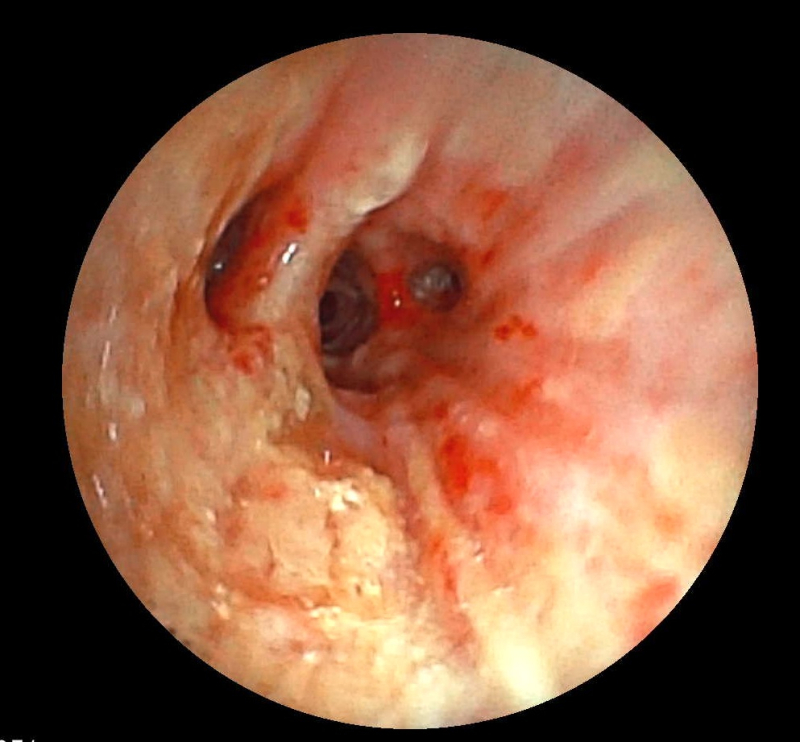

Ekip của bác sĩ CKI Phạm Thị Út Trang – Phó Trưởng Khoa Nội hô hấp đã phối hợp với bác sĩ gây mê hồi sức đã nhanh chóng tiến hành nội soi phế quản ống mềm, phát hiện dị vật góc cạnh khoảng 1cm là hạt kha tử hình bầu dục, bề mặt trơn nhẵn, hai đầu nhọn nằm chắn, gây bít tắc trong lòng phế quản gốc phải, ngay sát vị trí chia nhánh phế quản phân thùy- khu vực giải phẫu hẹp, góc rẽ nhánh phức tạp khiến việc gắp dị vật gặp khó khăn. Ekip nội soi can thiệp đã khéo léo tiếp cận và thành công gắp dị vật ra khỏi lòng phế quản. Sau can thiệp, sức khỏe của bệnh nhân ổn định, thở dễ dàng, không còn cảm giác tức ngực, được xuất viện sau 24h theo dõi.

Ekip can thiệp nội soi phế quản thành công lấy dị vật ra khỏi lòng phế quản